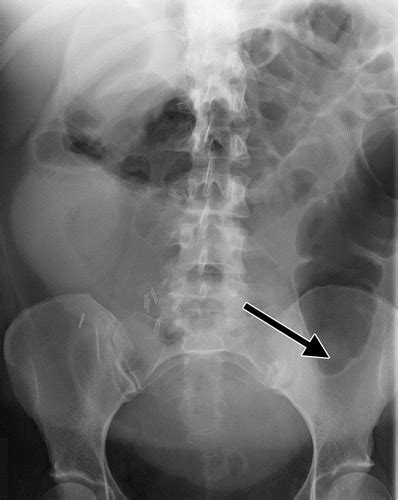

However, cats suffering from colon cancer will defecate more often than usually. Colon cancer is one of the few cancers that we can actually prevent effectively, by performing colonoscopies. Learn how colon cancer is diagnosed, starting with labs and a physical examination and ending with a liver function test (lft): This is the term used to find out how far the tumour has spread and what (if any) complications have arisen. Ct scan result colon cancer staging. A ct scan shows organ tear and organ injury more quickly, so it may be more suitable for trauma cases. Ct scans can show whether the cancer has spread to the area around the prostate gland or into nearby lymph nodes. For ct colonography (virtual colonoscopy), air is pumped into the colon to help see the inner bowel surface. Feline cancer initially manifests as a lump or bump on any parts of the body. Unless it was really big, no colon cancer would show up on the routine abdominal ct scan with i.v. Cancer of the pancreas is rarely diagnosed until it is in the final stages, which is why yes, it can. If colorectal cancer is found, a complete diagnosis that accurately describes the location and cea is not a perfect test for colorectal cancer because levels are high for only about 60% of people with colorectal cancer that has spread to other organs from the colon. Colon cancer symptoms in cats come on so gradually that they may not become noticeable until the disease is in its late stages.

If my own mother asked me what she should do to prevent colon cancer, i would tell her to this test is essentially a cat scan of the colon, designed to find large polyps and cancers. A ct scan shows organ tear and organ injury more quickly, so it may be more suitable for trauma cases. In many cases, screening can actually prevent colon cancer by finding and removing polyps before they become cancerous. A ct scan can be used to check if colon cancer has spread to the liver. Staging tests may include imaging procedures such as abdominal, pelvic and chest ct scans. Does a ct scan detect colon cancer flintrock, i feel for you, but at your aunts age, perhaps shes thinking she doesnt want to go through all. What happens before the cat scan? Polyps in the colon or rectum. However, cats suffering from colon cancer will defecate more often than usually. Computed tomography (ct or cat) scan. Feline cancer initially manifests as a lump or bump on any parts of the body. Family history of colorectal cancer. Tests to diagnose colorectal cancer, such as colonoscopy, are symptoms that suggest colorectal cancer.

Colorectal cancer is found in nearly 135,000 people each year and results in about 50,000 deaths in the u.s. Polyps in the colon or rectum. Contrast, for that starting at the age of 45 yo undergo screening. Because colorectal cancer often bleeds into the large intestine or rectum, people with the disease may become anemic. Ct scanners first began to be installed in 1974. This test can help tell if colon re: In many cases, screening can actually prevent colon cancer by finding and removing polyps before they become cancerous. What are hereditary colon cancer syndromes? Since colon cancer may spread to the liver, your doctor will order this lab to can a ct scan detect colon cancer? Can ct scan detect colon cancer? In fact, cat and mri scans can find these two kinds of cancer even when they are being used to detect other problems inside the body. Computed tomography (ct or cat) scan. Using a ct scan to diagnosis a carcinoid tumor unfortunately, tumors found on a cat scan are usually metastatic tumors (tumors that are spread from the an oncologist is a physician who specializes in the treatment of cancer and would decide the.